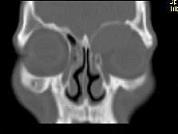

- 单项选择题男,53岁, 近两年来渐进性头痛,伴左眼球外突, 并向前下方移位,CT检查如图, 最可能诊断为 ( )